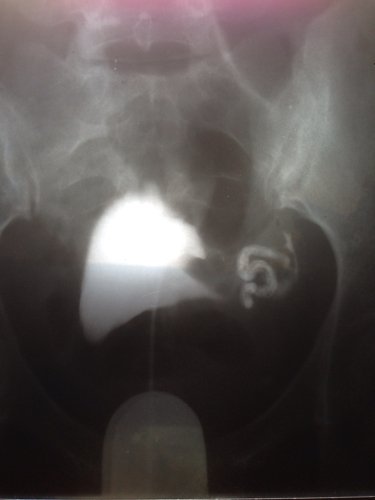

输卵管切了一边 请问另一边通畅吗 点击展开 匿名用户 2013-11-06 14:50 为您推荐: 其他回答 病情分析: 您好,如果未切除的输卵管没有堵塞问题,就能正常发挥其自身功能。 指导意见: 导致输卵管堵塞的因素有多种,可以向帮您检查治疗过的医生咨询治疗后的状况。 匿名用户 2013-11-06 15:00 相关问题 切了一边输卵管另一边伞端欠通畅 您好医生!我想咨询一下,我六月份查出输卵管一边堵一边通畅不良,医生给我开了胎盘片和促排卵的针,请问 孕育 一边输卵管切除,另一边又可能宫外孕了,以后是该要怎么生育好呢?现在怀孕34天,隔三天测了两